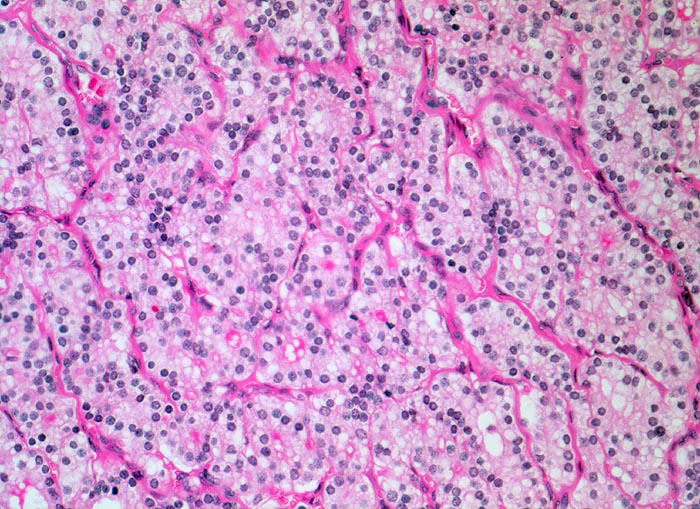

Die Follikel des endokrin aktiven Adenoms enthalten nur sehr wenig oder gar kein Kolloid. Die Zellen sind kubisch bis hochprismatisch und vielfach mehrreihig angeordnet.

Histologie

Vergrösserung

200